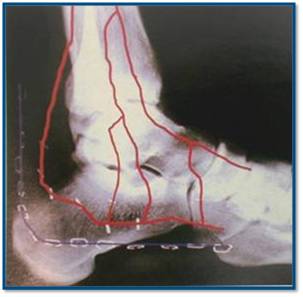

Точность репозиции суставной поверхности задней фасетки суставной поверхности пяточной кости на представленной вами рентгенограмме вызывает глубокие сомнения, так же как и конечный результат лечения в долгосрочной перспективе. По всей вероятности, у больного был перелом пяточной кости по классификации Sanders типа II A. Часть суставной поверхности задней фасетки, оставшаяся с sustentaculum пяточной кости (короткая линия на вложении, соответствующая субхондральному слоя репонированного фрагмента) находится на месте. А вот большая часть суставной поверхности так и осталась компримирована (длинная линия на вложении, соответствующая субхондральному слою компримированного фрагмента). При репозиции эти две линии должны совпадать. После репозиции, компримированный фрагмент следовало фиксировать к sustentaculum отдельным винтом (не всегда просто точно попасть). Пяточная пластина смещена к пяточному бугру, что не позволило фиксировать к ней самый проблемный участок пяточной кости – суставную поверхность. Не лишней здесь после репозиции была бы и костная пластика.

calcaneus 3.jpg